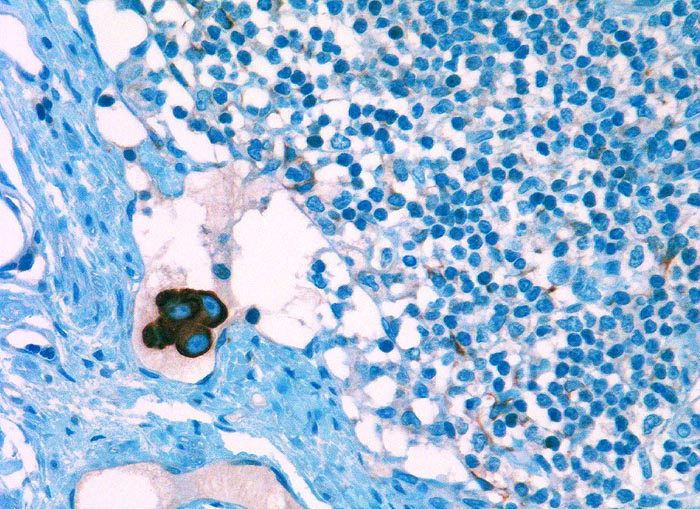

Tumor Einzelzellen in Lymphknotenrandsinus bei Mammakarzinom

Lymphknoten, Axilla

Stark positiv angefärbte Tumorzellgruppe in einem Randsinus des Lymphknotens. Die Tumorzellkerne tragen grosse Nukleolen. Im Lymphknotengewebe unspezifische Anfärbung von Reticulumzellen mit sternförmigen Zytoplasmaausläufern.

Metastase im Sentinellymphknoten.

Immunhistochemie

CK22